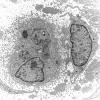

PERIPHERAL NEUROPATHY

4 AXONAL DEGENERATION

4 Macrophages